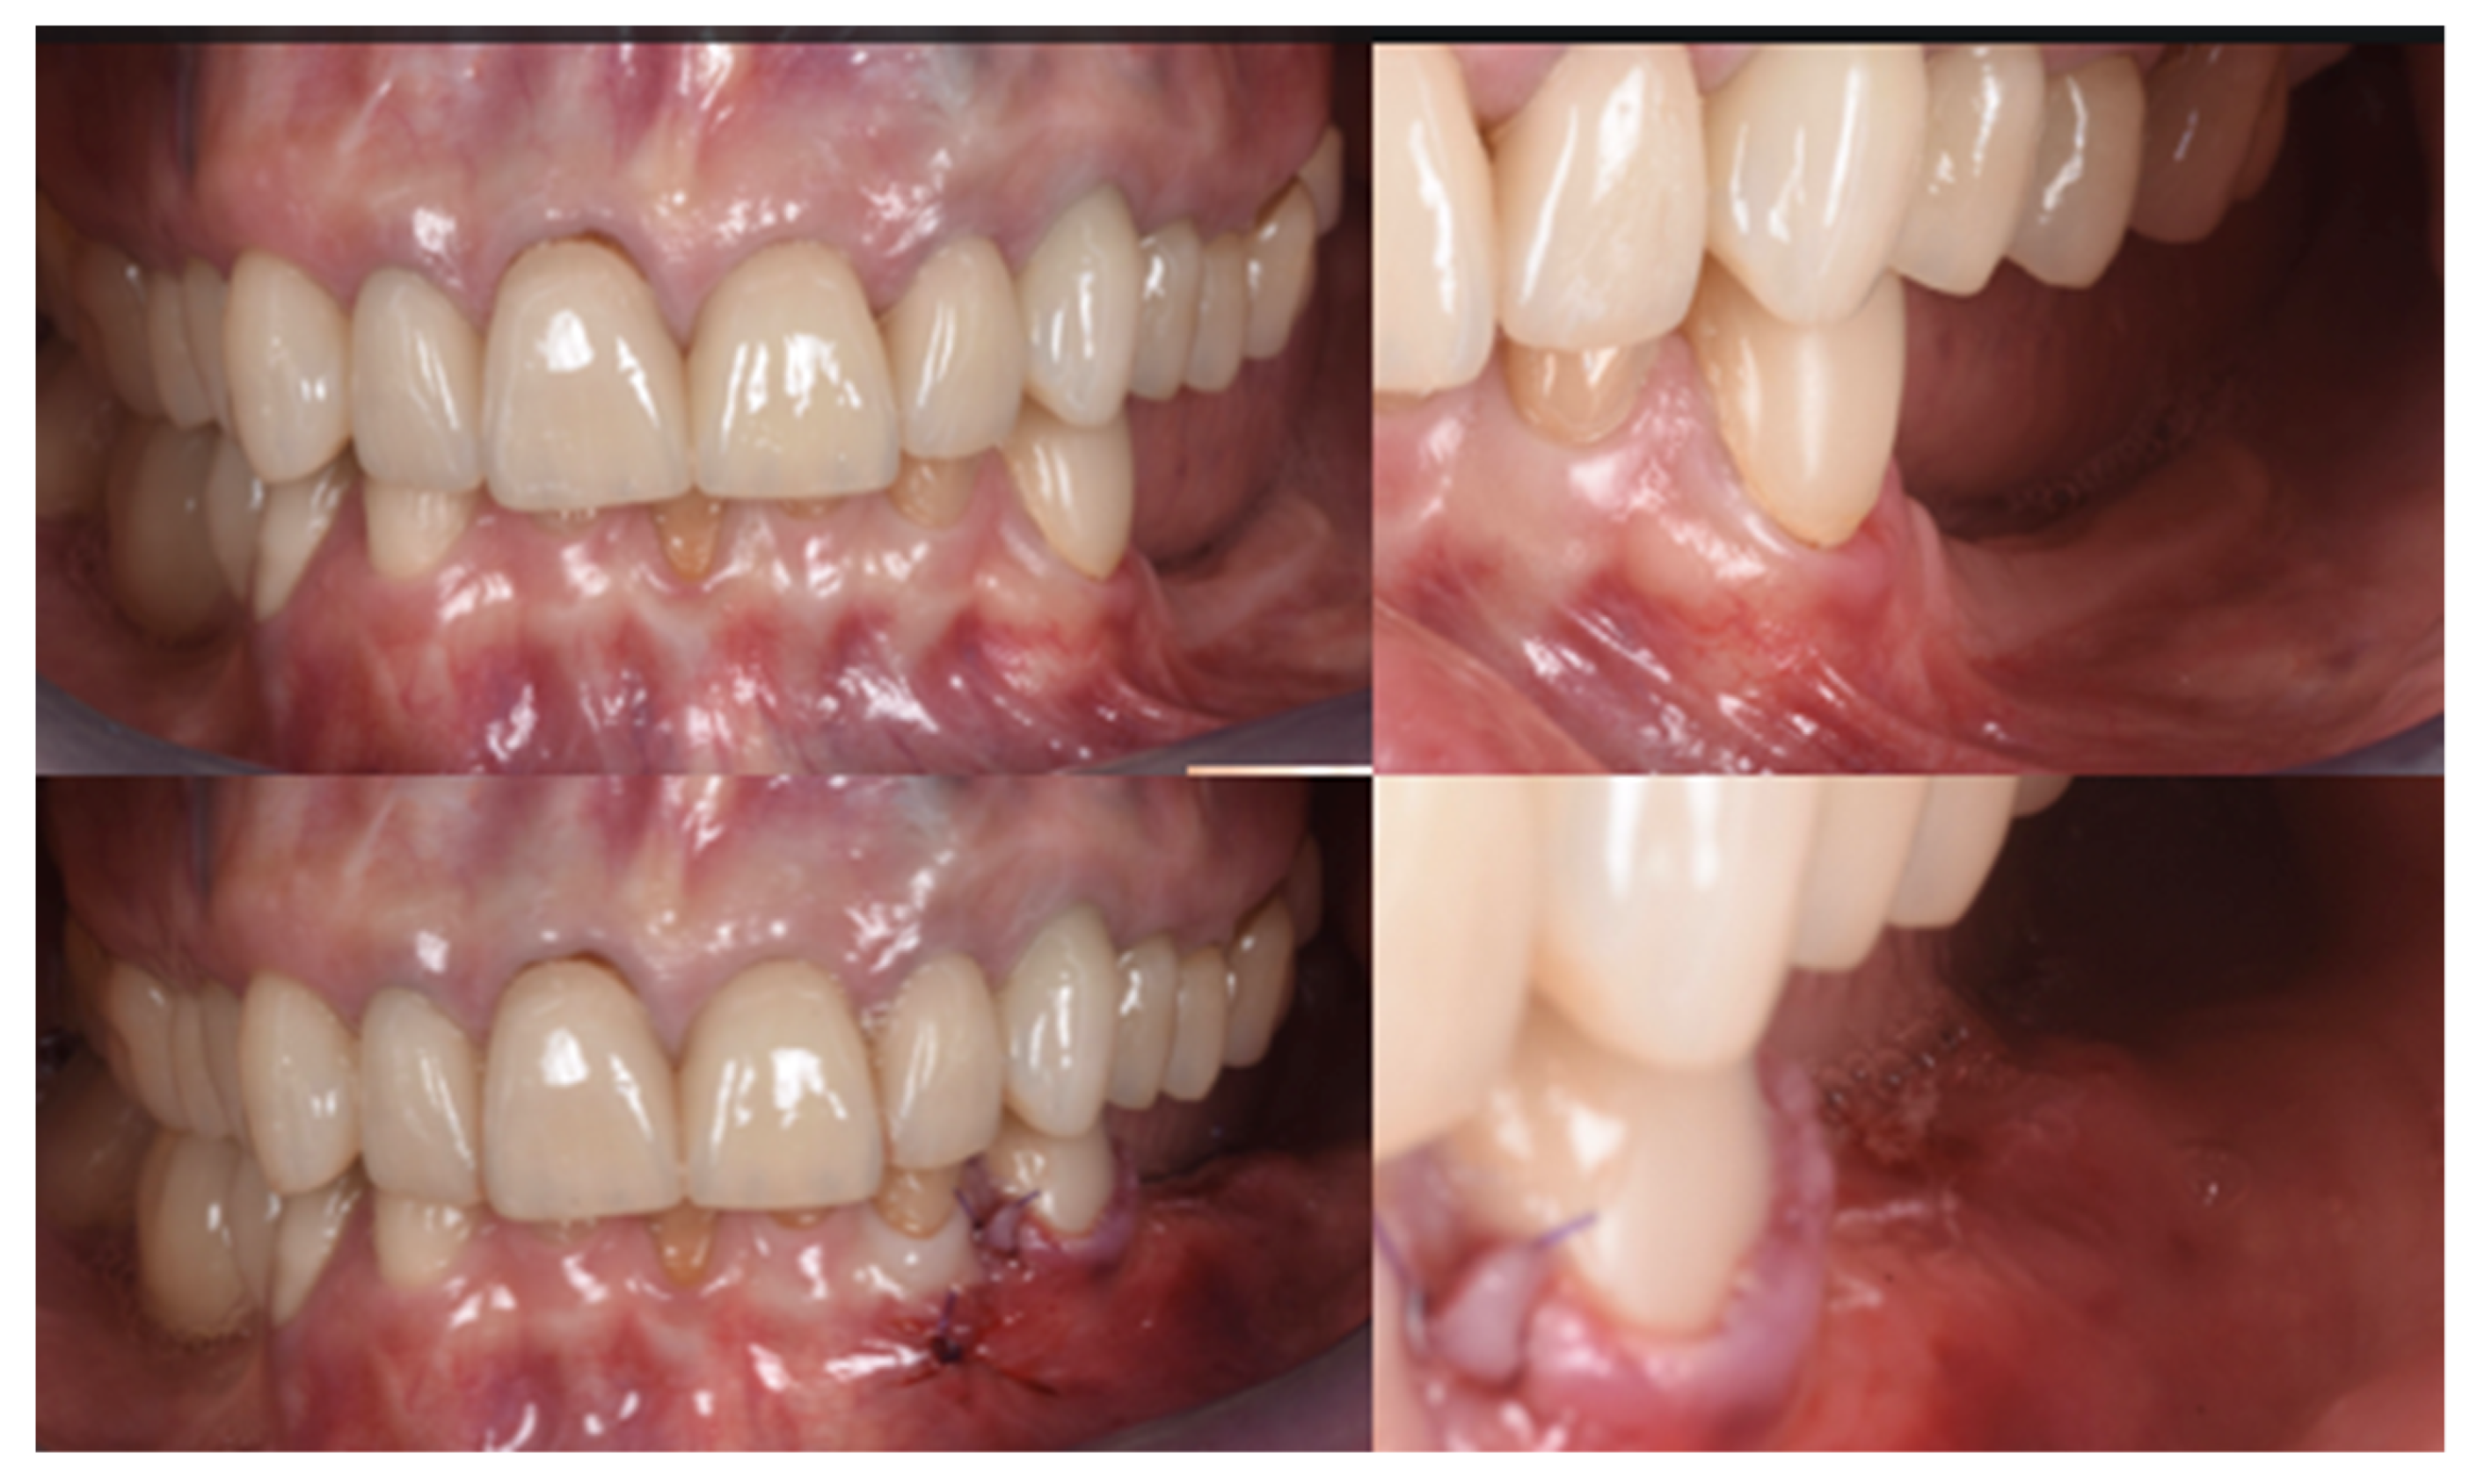

Two implants (Institute Straumann, Basel, Switzerland) of 4 × 12 mm and 5 × 8 mm were inserted in the 3.4 and 3.6 areas, respectively (Figure 9a). The final prosthesis was manufactured with a digital workflow and delivered after three months. The patient was monitored with clinical and radiographic evaluations 12 and 18 months after prosthetic loading. The clinical examination and the digital scans at 12 months of follow-up proved the efficacy of the regenerative approach (Figure 10 and Figure 11). The comparison between 12 (Figure 9b) and 18 month (Figure 9c) radiographs showed stability of the bone crest around the dental implants. Furthermore, a progressive mineralization of the regenerated area was also evident (Figure 9a–c).

Figure 10.

Clinical evaluation after 18 months of prosthetic loading.

Figure 11.

Scan taken after 18 months of prosthetic loading.